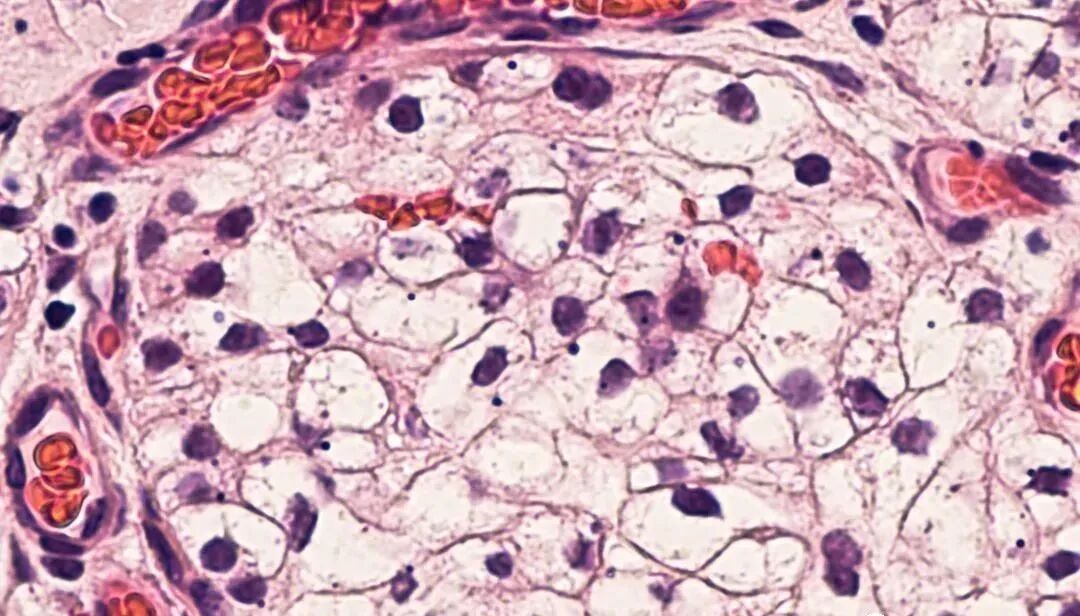

研究显示,静脉内注射的MSCs能够迁移到急性和慢性肾损伤模型动物的肾小球、肾间质、小管周围血管和肾小管。

图片

目前,外源性MSCs归巢到损伤动物炎症位点的分子机制还不是完全清楚。不过,趋化因子在炎症部位募集的增多很有可能是引导MSCs迁移的重要原因,此外,外源性MSCs的这种定向迁移和归巢方式与炎症部位趋化因子受体表达特征有关。